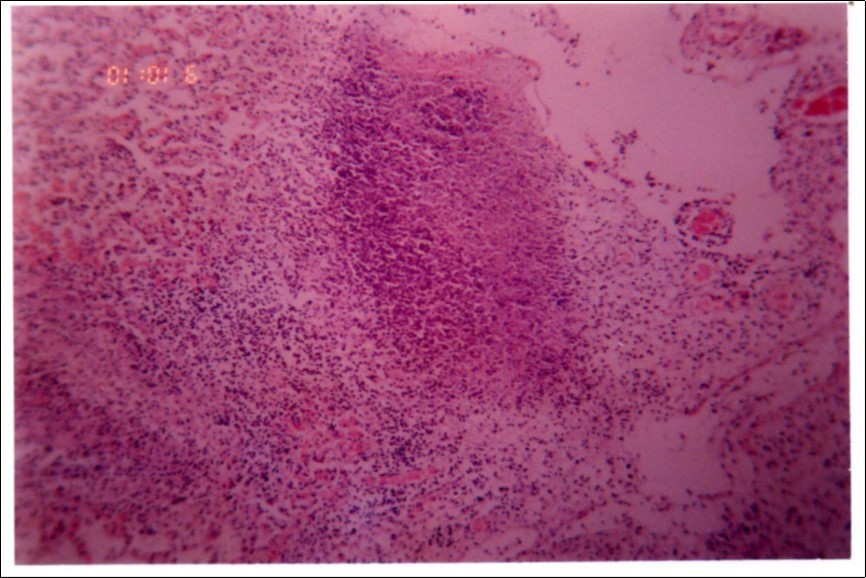

Histopathology

Figure 3, Figure 4 and Figure 5 show different histopathological pictures of hepatized lung tissue samples from which Mmm isolates were recovered. In Figure 3, widened interlobular septa, due to presence of fibrinous necrosis and cellular infiltration were observed. Figure 4 shows extensive loss of airspace due to necrosis and infiltration of neutrophils. Figure 5 shows hyperemia of alveolar wall capillaries and infiltration of few fibrin and neutrophils.

Figure 3.Widened interlobular septa in pneumonic lung tissue (H&E ×200).

Figure 4.Extensive loss of air space due to necrosis and infiltration of neutrophils (H&E ×100).

Although no advanced techniques like PCR were used to identify the isolates, procedures used in this study were quite enough to confirm the incidence. Affected animals with CBPP were diagnosed based on the clinical signs, the PM findings, the typical histopathological picture in addition to the isolation of the causative agent and its subsequent identification using cultural and biochemical procedures. Identification of the isolates was confirmed by the growth inhibition test as recommended in OIE manual 10. The histopathological sections of diseased lungs, from which Mmm (SC) was isolated, showed typical histopathological picture of CBPP. The CBPP lesion comprises abronchiolar necrosis and oedema which progress rapidly to an exudative serofibrinous bronchiolitis with extension to the alveoli and uptake of alveolar fluid into tissue spaces 17, lymphatic vessels and ultimately septal lymphatics 18. With stasis, lymphatic vessels become thrombosed and ultimately fibrosed 19. The histological section of the lung in acute stage of the disease showed odema in the lymphatics of the interlobular septa and interstitial tissue and massive infiltration of fibrin, macrophage and neutrophils into the alveolar lumen 20. Also there was presence of lymphocytes and alveolar macrophages around the lymphatic vessels and septa margin 21. These findings supported the isolation results and gave additional evidence for the diagnosis of the disease.